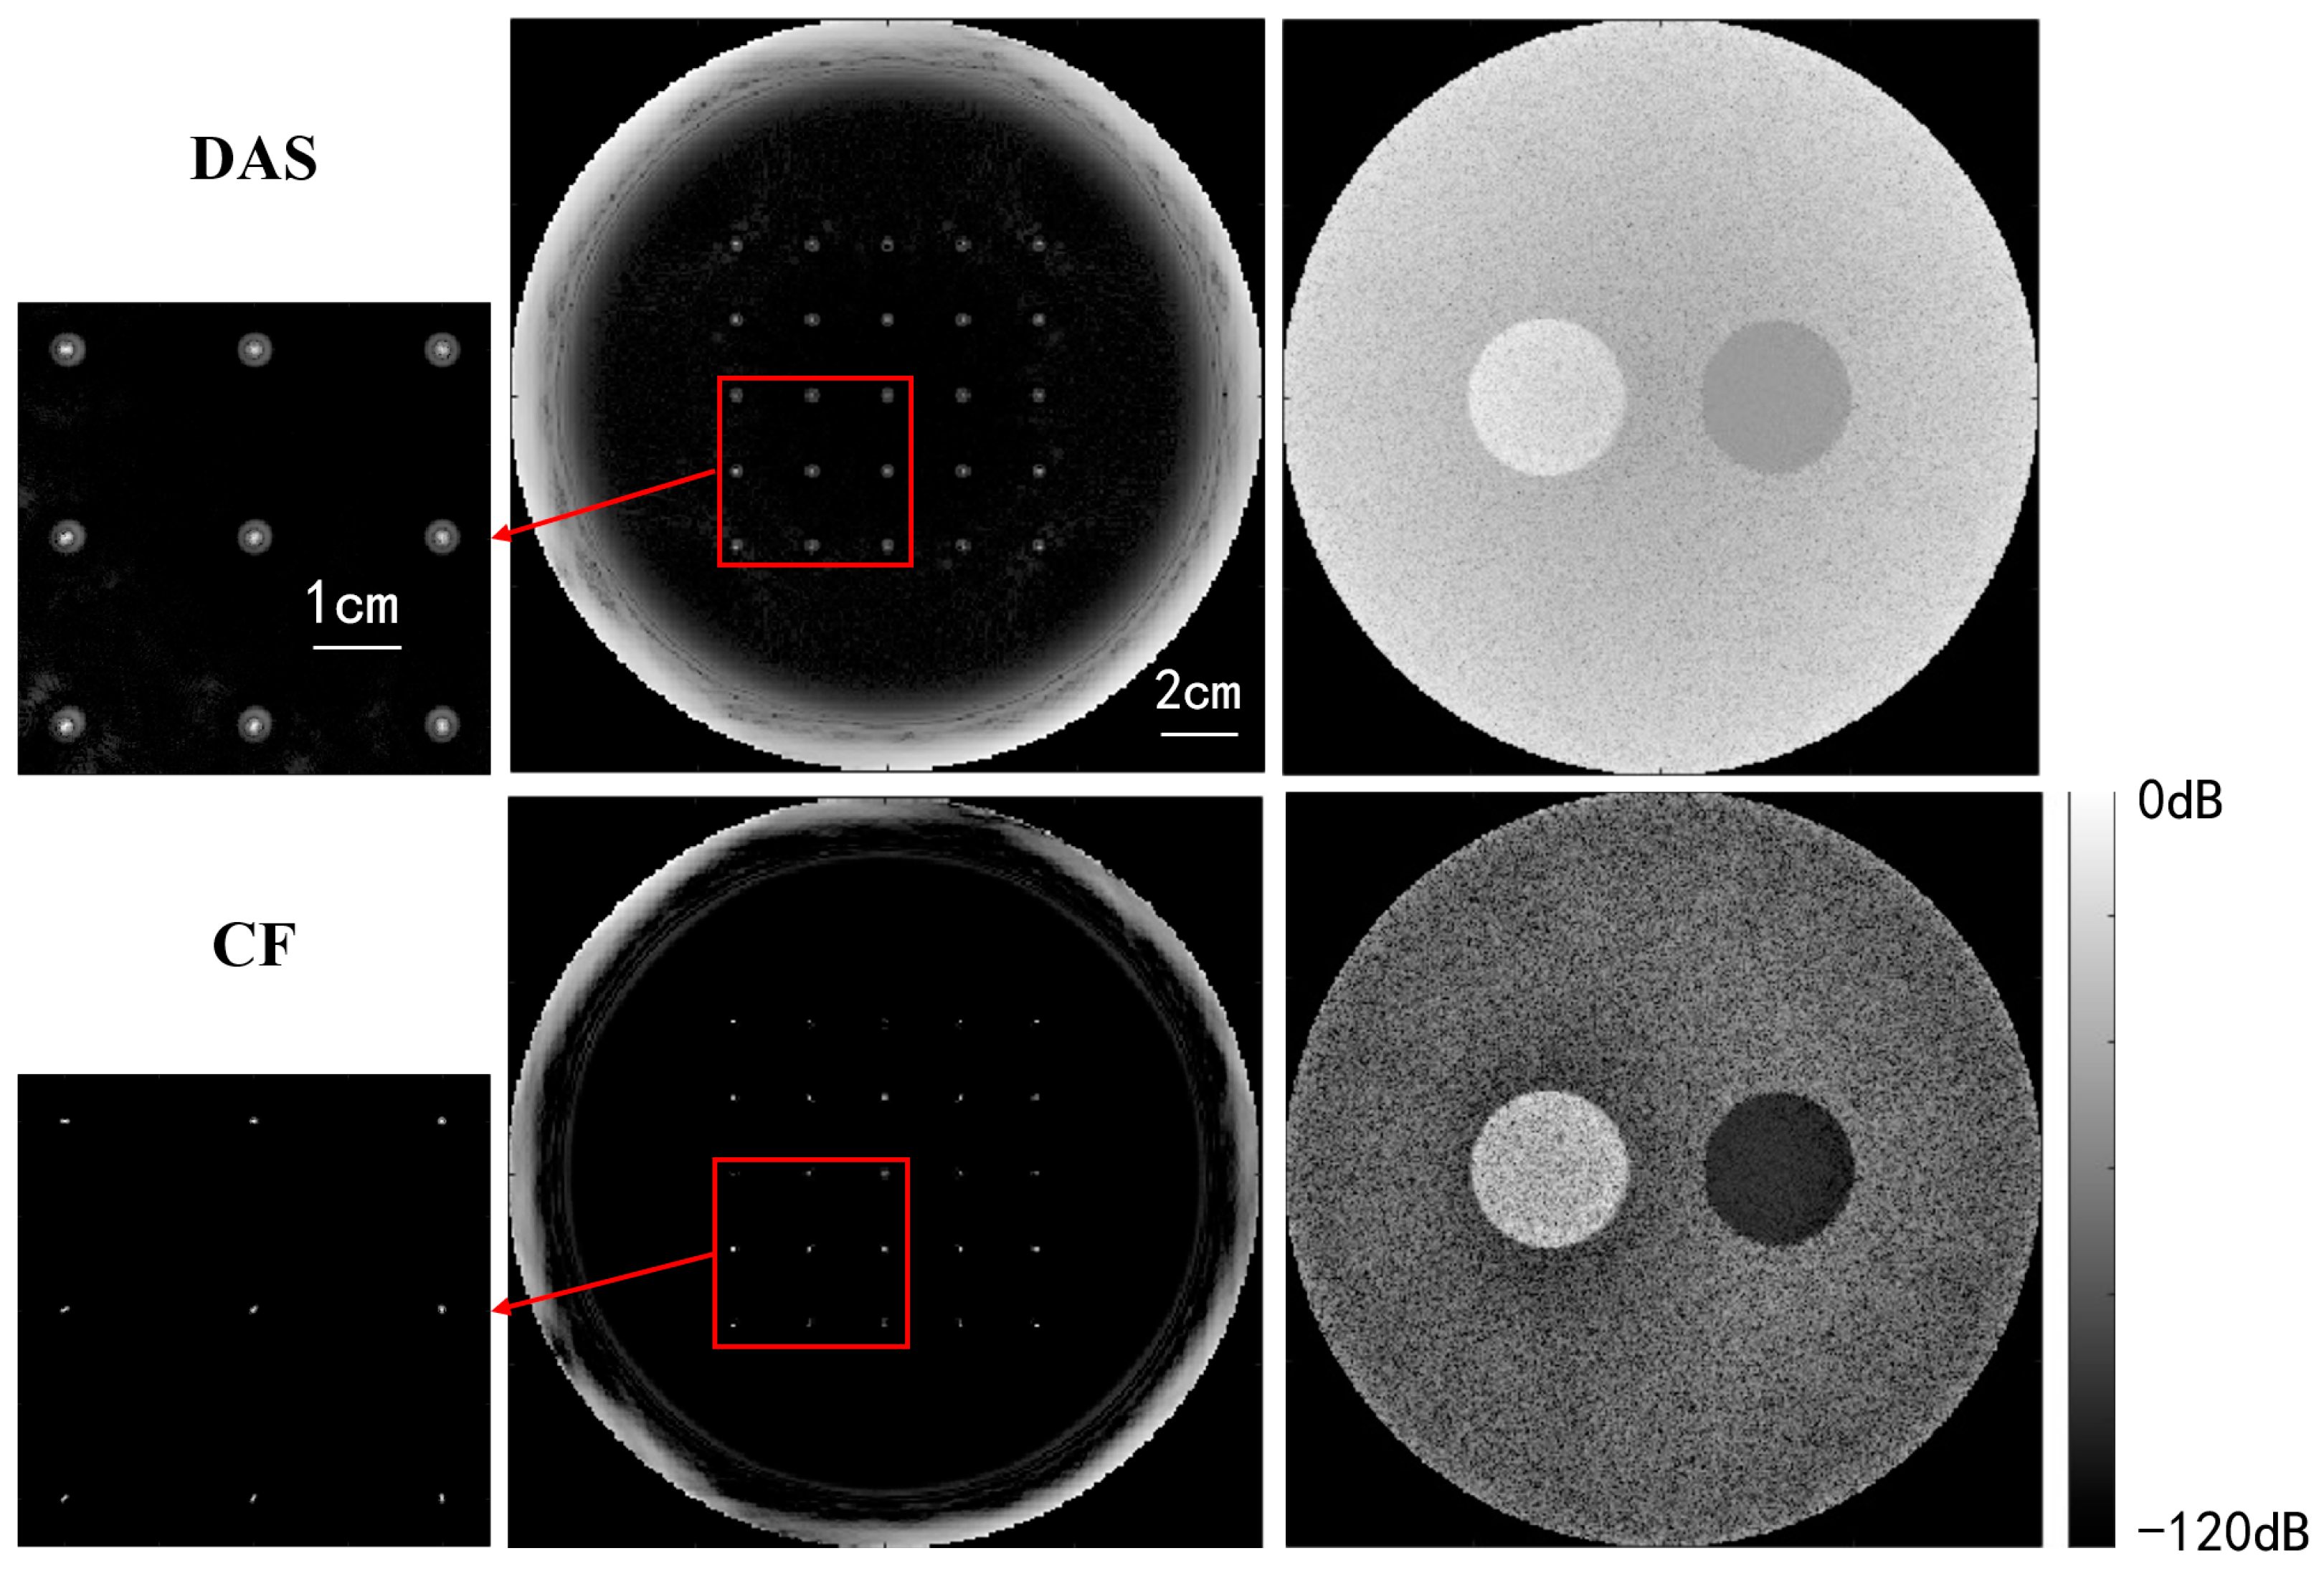

Figure 8 compares USCT reflection images obtained through DAS beamforming and CF beamforming. The reflection images include both point resolution evaluation images and circular contrast evaluation images, with simulation models provided in Figure 6. The images in the first and second rows were obtained through DAS beamforming and CF beamforming, respectively. Enlarged point resolution images highlight that CF beamforming produces significantly smaller point targets compared with DAS beamforming, indicating that CF beamforming can generate higher-resolution images. The circular contrast evaluation images further demonstrate that CF beamforming yields higher-contrast images.

Figure 8. Qualitative simulation image quality comparison between DAS and CF beamforming.